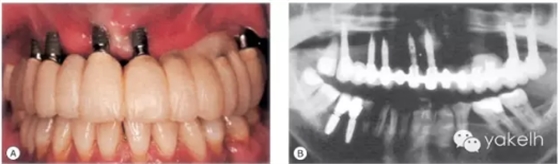

該患者上頜牙列缺失行種植修復(fù),種植體周圍存在嚴(yán)重骨喪失,造成了嚴(yán)重的美學(xué)問題(圖.14A)。大多數(shù)種植體周圍支持骨吸收達(dá)1/2義齒修復(fù)。

圖.14 (A)上頜牙列缺失行種植修復(fù),種植體發(fā)生廣泛的種植體周圍炎。(B)影像學(xué)檢查進(jìn)一步證實(shí)UL4、UL5種植體已脫落。